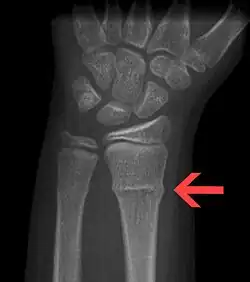

A Torus fracture, also known as a buckle fracture is the most common fracture in children.[1] It is a common occurrence following a fall, as the wrist absorbs most of the impact and compresses the bony cortex on one side and remains intact on the other, creating a bulging effect.[2] As the bulge is only on one side of the bone, this injury can be classified as an incomplete fracture. The compressive force is provided by the trabeculae and is longitudinal to the axis of the long bone, meaning that the fracture itself is orthogonal to that axis.[3] The word "torus" originates from the Latin word "protuberance."[4]

Buckle fractures can be identified by performing a radiograph. The diagnosis of a torus fracture is made from both anterior/posterior and lateral projections. The typical features include:

- The buckling of cortical bone, which may appear as a small bulge or protuberance in the radius or ulna.

- The bone may have a slight angulation.[8]